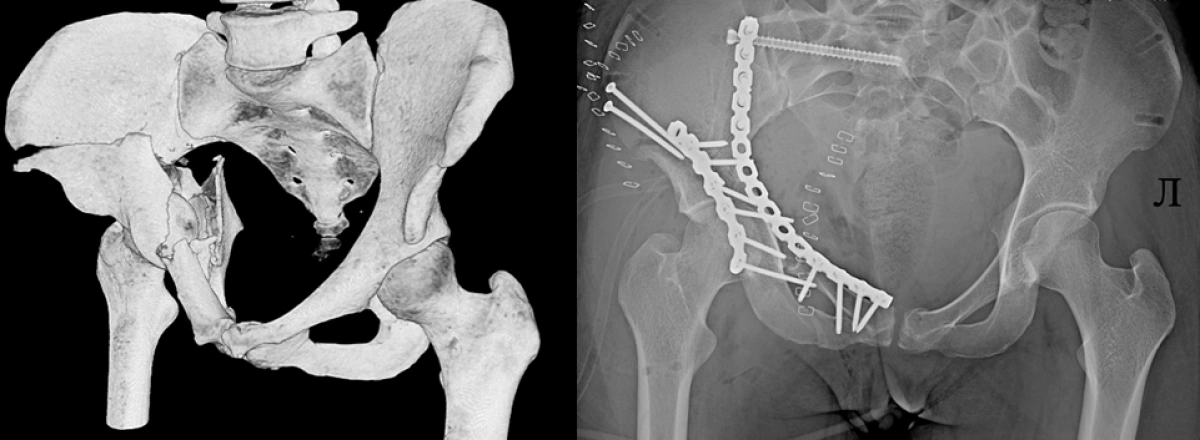

Лечение таких повреждений чрезвычайно сложное и длительное. Оно включает многоэтапные операции, иногда продолжительностью пять часов, использование наружных фиксаторов и имплантатов, длительный период восстановления. Так, в 14 травматологическое отделение больницы поступила 25-летняя пациентка — пострадавшая при катании на «неофициальном» спуске врезалась в бетонный блок. Диагностированы были множественные переломы костей таза. Итог — реанимационное отделение, а после стабилизации состояния – повторная 5-часовая операция: многочисленные переломы были установлены в правильном положении и фиксированы металлоконструкциями. Теперь ее ждет длительная реабилитация.